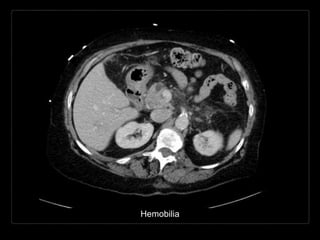

HEMOBILIA

Presencia de sangrado hacia el

árbol biliar y sangre en la bilis.

• Causas:

• trauma/biopsia

• enfermedad inflamatoria

• colelitiasis

• tumor

• anormalidades vasculares

Hallazgos por TC y RM

• contenido con densidad/intensidad hemática

• contenido heterogéneo de la vesícula biliar

• posición dependiente

• vesícula distendida con engrosamiento de su

pared

• + C

• reforzamiento de la pared vesicular

T2 Fat Sat - Hemobilia